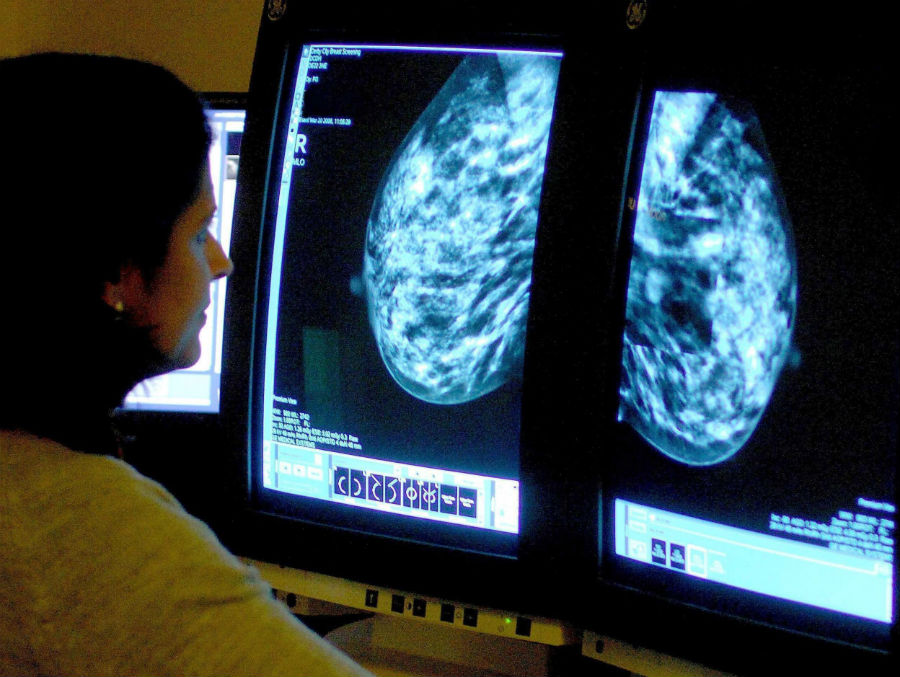

Регулярные обследования позволяют выявить рак молочной железы (РМЖ) на ранней стадии, еще до появления симптомов — и до 98% женщин выздоравливают, если его выявили вовремя и правильно лечили. Каждой женщине важно знать, относится ли она к группе высокого или среднего риска, поскольку от этого зависит, как часто она должна проходить профилактические обследования.

Женщина относится к группе высокого риска, если ее ближайшие родственники, мама или бабушка, перенесли рак груди или другие онкологические заболевания репродуктивной сферы, особенно в молодом возрасте. В этом случае врач-маммолог составит индивидуальную программу после 20 лет. Если женщина относится к группе среднего риска и ее ничего не беспокоит: нет никаких изменений в молочных железах, жалоб или симптомов, — до 40 лет нет необходимости проходить специальные обследования. Однако, как подчеркивают специалисты, при любых изменениях по сравнению с нормой следует не откладывая обращаться к врачу — гинекологу или онкологу-маммологу.

Стоит ли во время планирования беременности проходить дополнительный скрининг на рак молочной железы «для перестраховки»? Есть случаи, когда это действительно имеет смысл, но чаще всего, если пациентка регулярно проходит осмотр в положенное время, это лишнее, говорит химиотерапевт Клиники амбулаторной онкологии и гематологии Александр Аболмасов.

«Вероятность [развития рака молочной железы] существует даже после обследования. Ни у какого метода исследования нет 100%-ной гарантии: мы можем сделать исследование, которое увидит маленькое образование, но никогда не сможем сделать исследование, которое увидит клетку, десять клеток, сто клеток. Везде есть пороговая разрешающая способность, поэтому такие риски существуют», — отмечает эксперт.